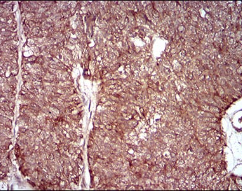

IHC    1/200 - 1/1000